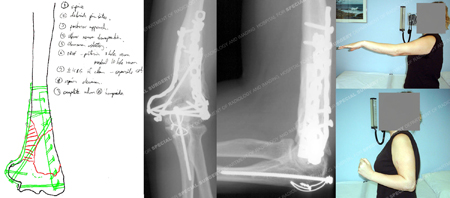

Pre-operative plan (left image) for placement of bone graft and plate and screw fixation placed in

a 90/90 fashion; x-rays at 25 months (2 middle images) illustrating a healed distal humerus fracture;

clinical images at 25 months (images on top-right and top-bottom) and illustrating excellent range of motion.